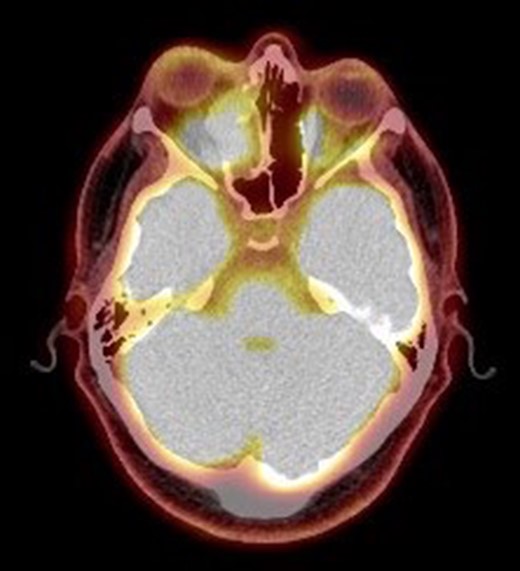

On radiological evaluation, CT scan with contrast of the paranasal sinuses (PNS) revealed a mass involving the right ethmoid sinus with medial wall and orbital floor extension (Fig. 2). The subsequent magnetic resonance imaging (MRI) revealed an infiltrative soft tissue mass occupying the right ethmoid sinus, eroding inferio-medial orbital wall and extending to the extracoanal space (Fig. 3). Positron emission tomography (PET) scan demonstrated an ill-defined 4.5 × 4.2 cm2 mass lesion in the right nasal cavity and ethmoid sinus extending to the right medial orbital floor (Fig. 4). The scan did not reveal any associated lymphadenopathies.

Positron emission tomography scan. PET scan showing an ill-defined 4.5 × 4.2 cm2 mass lesion in the right nasal cavity, maxillary and ethmoid sinuses extending to the right medial orbital floor.